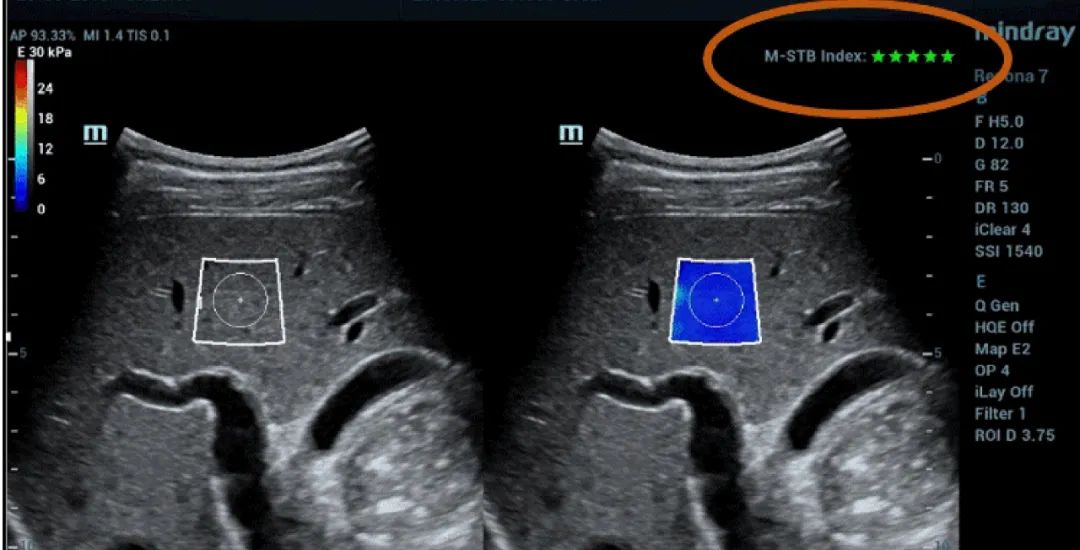

Afbeelding 1 (vervolgd): (e) Beelden verkregen met 2D SWE (STE; Mindray, Shenzhen, China). Er worden twee kwaliteitscriteria gegeven: de index voor bewegingsstabiliteit (M-STB), die wordt aangeduid met sterretjes (de hoogste stabiliteit wordt aangeduid met vijf groene sterretjes), en het betrouwbaarheidsraster (RLB: reliability), dat van paars naar groen gaat, waarbij groen de hoogste betrouwbaarheid aangeeft. De sterretjes zijn een indicator van beweging tijdens de verwerving. Bij minder dan vier sterretjes is er aanzienlijke beweging tijdens de verwerving en dat frame mag niet worden gebruikt voor de meting van de leverstijfheid. (f) Verkregen beelden.

De M-STB-index geeft de stabiliteit van de weefselbeweging aan die wordt veroorzaakt door de ademhaling van de patiënt of door compressie van de operator. Dit helpt bewegingsinterferentie te elimineren. Dit wordt aangegeven door sterretjes (de hoogste stabiliteit wordt aangeduid met vijf groene sterretjes). Een betrouwbaar beeld moet ≧4 groene sterretjes hebben.